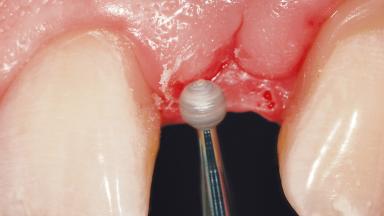

Peri-Implant Mucositis Treatment Outcomes on an Implant with a Submucosal Restoration Margin

Mauricio Araujo and Flauvia Matarazzo present this straightforward clinical case, demonstrating the potential effect of implant placement depth on the resolution of peri-implant treatment. A 42-year-old systemically healthy female patient, a non-smoker with no history of periodontitis, was treated at the Dental Clinic at the State University of Maringá, Brazil between 2008 and 2009, when she received five implants restored with single crowns at sites 14, 26, 27, 36, and 46. After delivery of the implant-supported prosthetic restorations, the patient was enrolled in the supportive peri-implant therapy (SPiT) maintenance program at the same university.